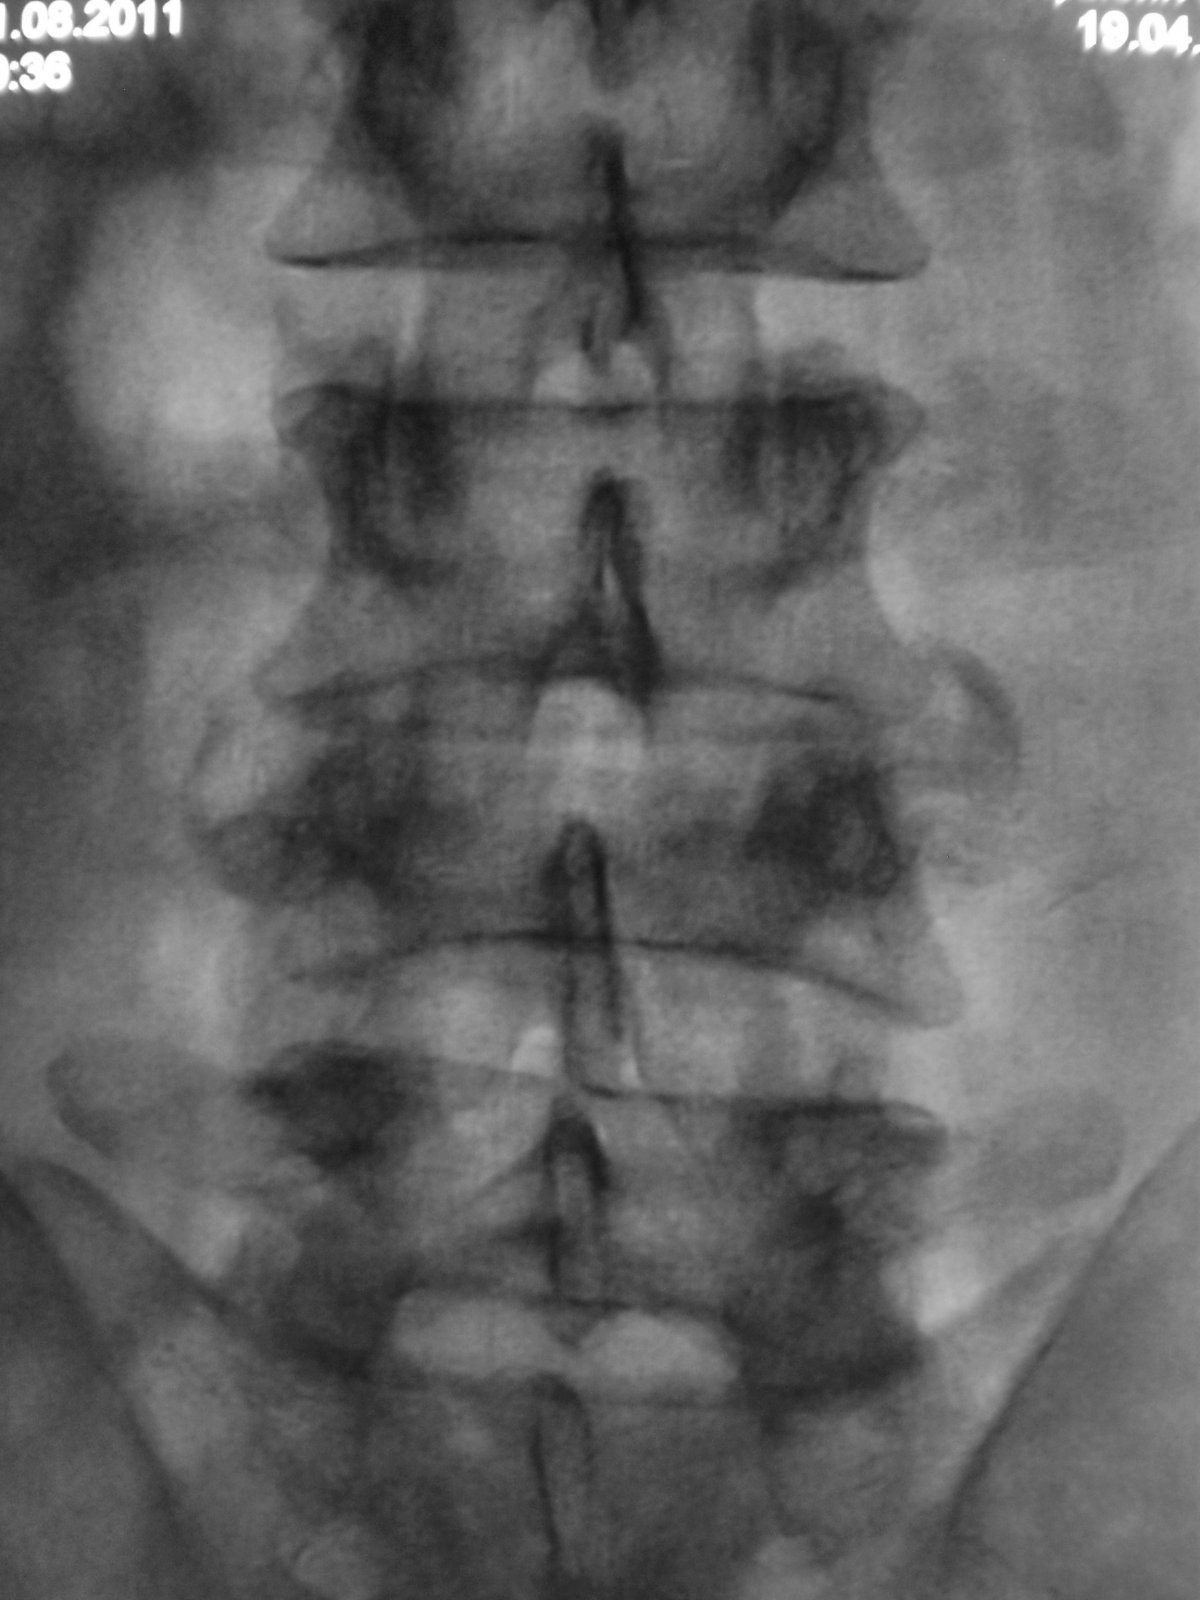

Компрессионный перелом L4. Клин Урбана сдавливает элементы конского хвоста. Синдром конского хвоста(?). Необходима срочная декомпрессия.

пишут не рентгенологи, а клиницисты. О сдавливании элементов хвоста, кроме клиницистов, могут еще судить магниторадиологи. Наш (общий на всех) термин - стеноз позвоночного канала. Еще надо не лениться и указать степень компрессии компрессии тела - легкая (20-25%), умеренная (25-40%), выраженная (больше 40%). А также замерить расстояние между основаниями дуг позвонков в прямой проекции - у L4 оно явно шире, и тогда в дополнение к перелому тела добавится перелом дуги и термин "нестабильный". Для полной красоты следует указывать угол кифотической деформации; критическими значениями являются:  для шейного отдела - 11º,  для грудного – 40º,  для поясничного - 25º

а здесь еще и переломовывих L4. а перелом еще и оскольчатый. с такой картиной можно утверждать что инвалидизация пациенту светит.А в S4 я перелома не вижу.